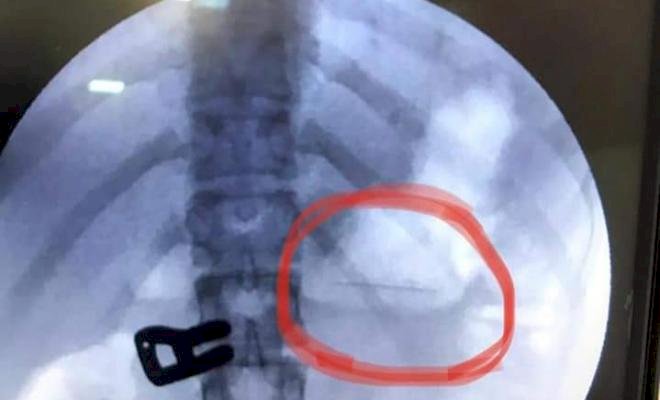

تمكن الطاقم الطبي برئاسة رئيس قسم مناظير الجهاز الهضمي بمجمع ناصر الطبي في غزة ، د.علاء الشاعر من استخراج دبوس بطول 2 سم من معدة فتاة تبلغ من العمر 16 عام، حيث وصفت بالصعبة وذات خطورة عالية.

وأوضح الشاعر أن المريضة حضرت الي قسم المناظير بعد ابتلاعها لدبوس، وأجريت لها صورة الأشعة وتبين أن الدبوس عالِق في المعدة، وقد أجريت لها على الفور عملية منظار للمعدة واستخراج الدبوس بعناية تامة دون تعرّض المريضة لمضاعفات أثناء استخراجه وذلك لعدم توفر الامكانيات المناسبة لمثل هذه العمليات بسبب النقص الحاد في مستلزمات المناظير استطاعت المريضة مغادرة قسم المناظير بعد ساعة من اجراء العملية وهي بصحة جيدة.